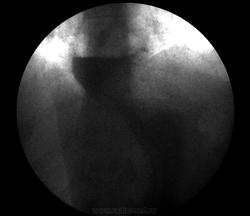

Можно даже без натуживания, лежа на животе с приподнятым левым боком. Например, так (см.)

Приложения:

07_gpod.jpg